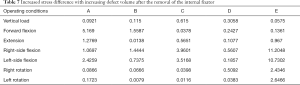

Under each working condition, as the defect volume increased, the stress differences between consecutive groups were as listed in Table 4.

Full table

We used the data to generate a dot plot to more intuitively show the relationship between the defect volume and the increase in stress (Figure 14).

The 5/5 defect in the anterior column of the injured vertebra was a simulated extreme condition that does not exist in actual clinical practice, so we removed this condition from consideration. According to the chart, after the implantation of the internal fixator, the stress increased significantly when the injured vertebra showed a defect. As the defect volume increased, the stress increased correspondingly, and the increase in stress represented by group D (stress difference between the 3/5 defect group and the 4/5 defect group) was the greatest.

When the removal of the internal fixator was simulated, the stress outcomes of the five types of superior endplate collapse (defect volumes of 1/5, 2/5, 3/5, 4/5, and 5/5 of the anterior-two-thirds edge of the vertebral body, respectively) under vertical load, anteroposterior flexion, lateral flexion, and left and right rotation conditions. The stress distribution maps are shown in Table 6. We also made a table of the stress difference between the two groups in Table 7 and generated a dot plot (Figure 15). It can be seen that with the removal of the internal fixator and the loss of support from the internal fixator as well as the increase in defect volume, the stress gradually grew larger. The dot plot of the difference between groups showed that as the stress increased, the magnitude of change in the combined stress represented by group C (stress difference between the 2/5 defect group and the 3/5 defect group) under the seven working conditions was the largest, suggesting that after the removal of the internal fixator from injured vertebrae with superior endplate collapse and bone defect, when the collapse defect area reached 3/5 of the anterior column of the vertebral body, the concentration of stress increased significantly. This suggests that the risk of continued compression or even refracture of the injured vertebra increases after the removal of the internal fixator.